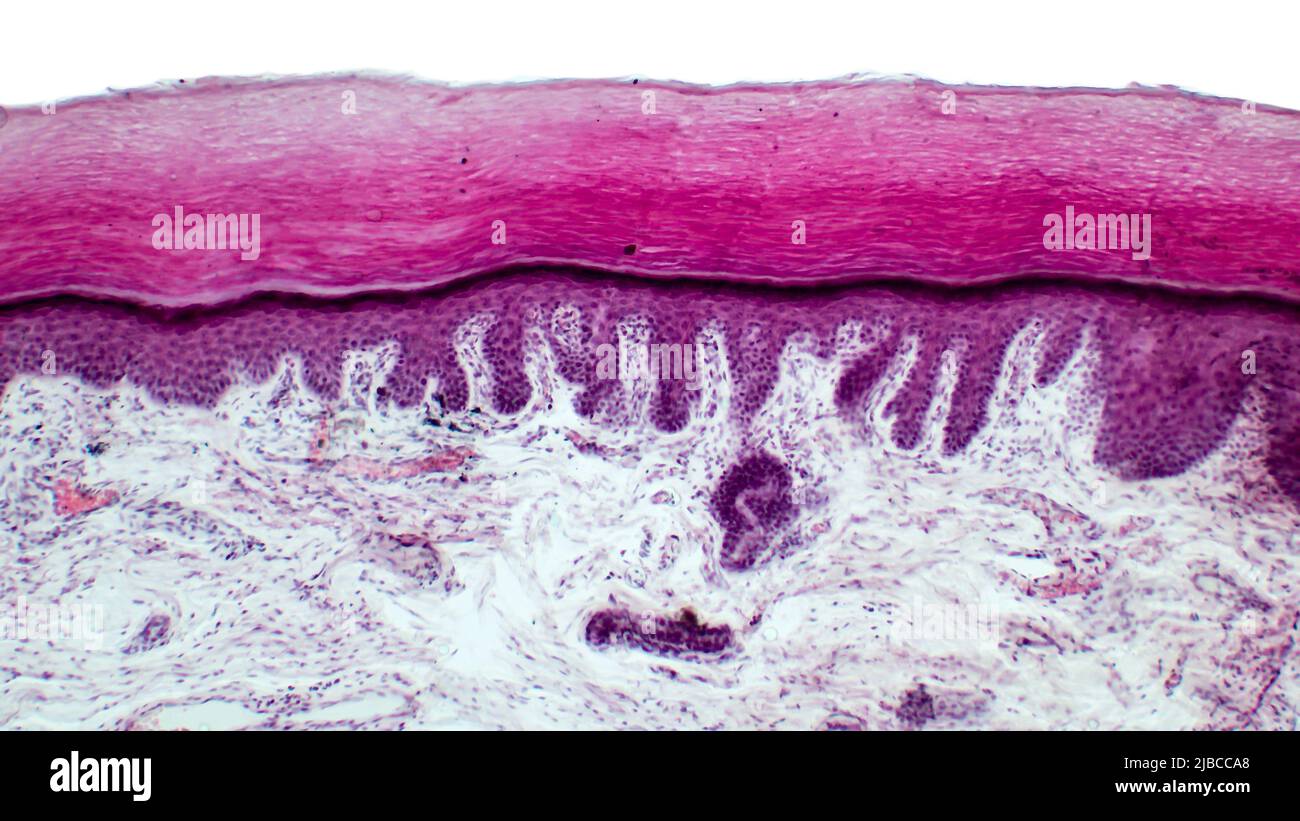

Kleine Verfärbung der Epidermis beim Menschen beschreibt geringfügige Veränderungen der Hautfarbe, die in der Epidermis, der äußersten Hautschicht, auftreten. Diese Veränderungen können sich in Form von Flecken, Punkten oder Bereichen unterschiedlicher Pigmentierung äußern. Sie sind in der Regel harmlos, können aber auch ein Hinweis auf tieferliegende medizinische Zustände sein.

Die Art der Pigmentierung spielt eine wichtige Rolle. Hyperpigmentierung bedeutet eine Zunahme der Pigmentierung, was zu dunkleren Flecken führt. Im Gegensatz dazu bedeutet Hypopigmentierung ein Verlust der Pigmentierung, was zu helleren Flecken führt. Die Art der Pigmentierung hilft bei der Diagnose der Ursache. Manche Verfärbungen zeigen eine Mischung aus beiden.